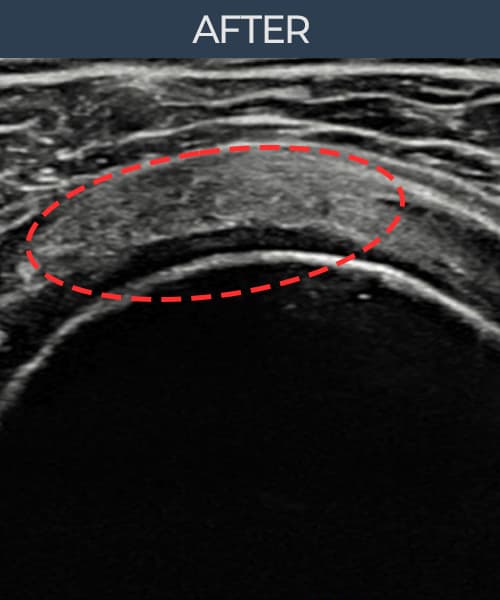

超音波検査にて腱板 部分断裂+靭帯損傷(11mm × 6mm (腱厚の約58%欠損))を確認。縫縮術施行後、腱の連続性が回復し、日常生活に復帰されました。

施術後

術前超音波にて腱板 部分断裂+靭帯損傷・肩棘上筋腱のエコー不連続と腱欠損(11mm × 6mm (腱厚の約58%欠損))を確認。術後超音波では断裂部位が再生組織で充填され、腱の連続性回復とエコーパターンの正常化が確認されました。

持続する肩痛で来院された患者様です。超音波検査にて腱板 部分断裂+靭帯損傷(欠損:11mm × 6mm (腱厚の約58%欠損))を確認し、超音波ガイド下で非手術的縫縮術を施行しました。術後は約4〜6週間のブレース装着の後、段階的なリハビリプログラムを実施。経過超音波で腱の連続性回復を確認し、患者様は無事に日常生活へ復帰されました。